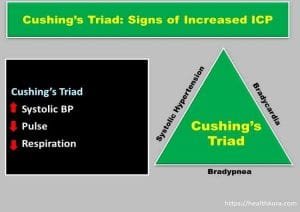

late sign of increased intracranial pressure